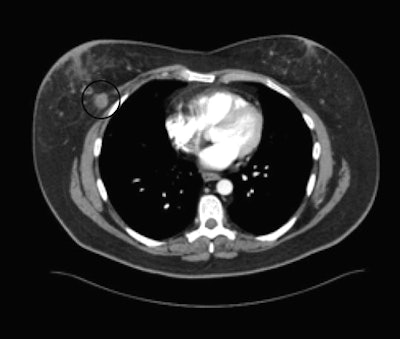

![]() |

| Incidental breast lesion visible at CT (circled) could not be seen at repeated mammography targeted for this finding. All images courtesy of Dr. Jeffrey Mendel. |

Why are so many breast cancers seen for the first time on CT? For one thing, mammography at its best sees only 85% of breast lesions, he said. Many patients, particularly those with recurrent illness, don't undergo routine screening mammography. To find breast cancers, radiologists should remember that every chest CT is also a breast tomogram. Contrast enhancement can reveal more lesions.